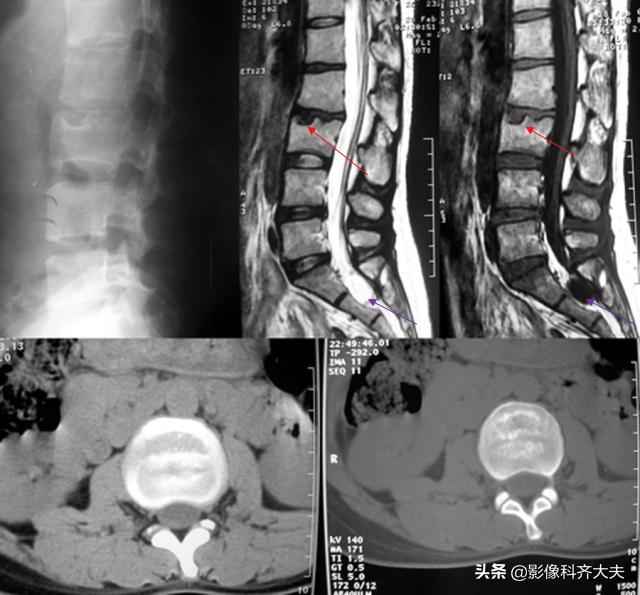

正侧位示腰4、5间隙变窄,CT扫描示腰4、5间盘突出

CT:椎间盘突出(中央型)

Schmorl结节(许莫氏结节)

Schmorl结节(许莫氏结节),是椎间盘退变时,软骨板变薄及玻璃样变,甚至消失。髓核经软骨板的薄弱或者缺损部疝入椎体内,在椎体内形成软骨结节。

是髓核于椎体上面或者下面形成的圆形或者半圆形的骨质凹陷区,其边缘有硬化。可对称见于相邻两个椎体的上下面,并且可以累及多个椎体。

可以说算是一种特殊类型的椎间盘突出。只不过不像普通椎间盘突出是突出于椎体后缘,而是突出到上下椎体里!

在影像上看,椎体上下缘弧形的凹陷或者骨性透亮区,伴有不同程度的边缘硬化,广泛硬化时椎体呈象牙质样。

许莫氏结节并骶管内囊肿